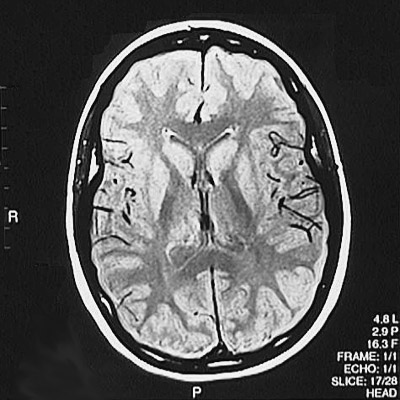

This is a normal axial proton density MRI scan demonstrating the frontal lobe and parietal lobe and genu of corpus callosum and splenium of corpus callosum and anterior horn of lateral ventricle and posterior horn of lateral ventricle and caudate and thalamus and putamen and internal capsule and superior sagittal sinus.